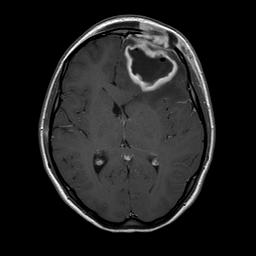

Dopo 10 giorni Martina ripete RMN di controllo (Figura 3) che documenta una marcata riduzione della lesione (diametro 35 x 24 x 18 mm) e una lieve diminuzione dell�edema perilesionale.

Figura 3. Lesione in sede frontale ipointensa nelle sequenze T1 pesate, di diametro 35 x 24 x 18 mm, circondato da cercine caratterizzato da marcato enhancement. Nelle sequenze T2 il cercine perilesionale appare ipointenso (a causa della presenza di collagene, emorragia e radicali liberi paramagnetici). Quadro complessivamente ridotto rispetto ai controlli precedenti. Ridotto l�effetto massa sul sistema ventricolare omolaterale.